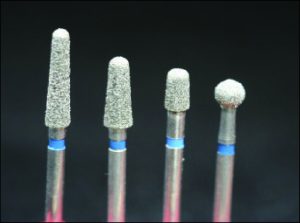

The occlusal rest seat can be prepared with rond burs, round-tipped or progressively narrower diamond burs (Fig. 10-34). When using a round diamond bur, care must be taken not to create an undercut in the rest seat (Figure 10-35). Round-tipped and progressively narrower burs allow for preparation without creating an undercut (Fig. 10-36).